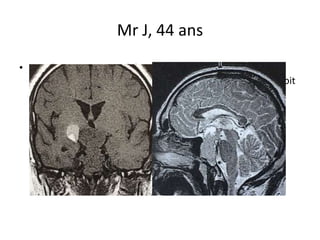

Mr J, 44 ans

• #3 IRM: adénome de 50 mm de hauteur avec extension latérale et composante kystique Anomalies du CV objecitvées au CV à type de

• #5 IRM: adénome de 50 mm de hauteur avec extension latérale et composante kystique

• #6 IRM: adénome de 50 mm de hauteur avec extension latérale et composante kystique